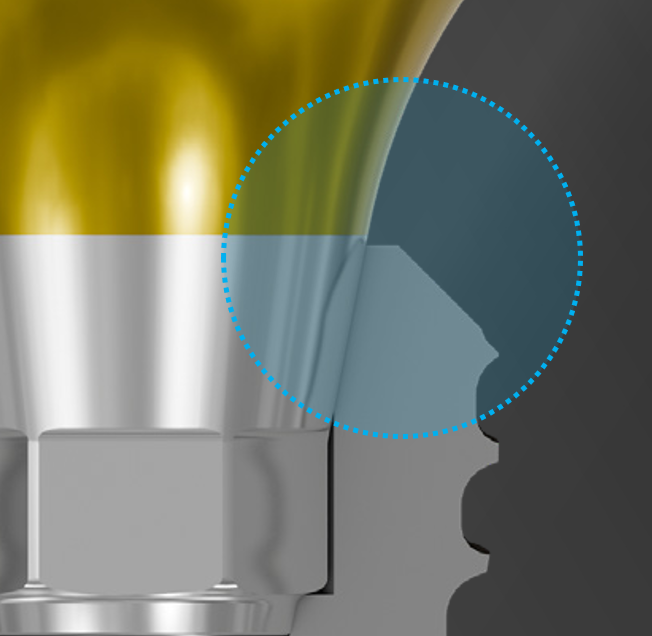

Tissue Contour Abutment Design

Designed to support a natural emergence profile and ensure harmonious soft tissue adaptation.

The optimized contour promotes long-term soft tissue stability, improved esthetics, and predictable peri-implant health.